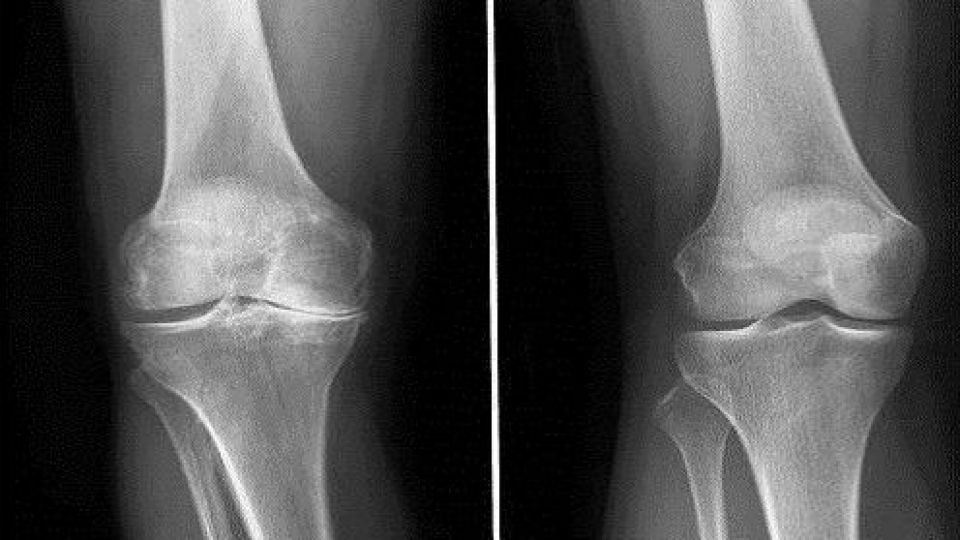

مدیر درمان مرکز سلول درمانی پژوهشگاه رویان بیان کرد: شیوع استئوآرتریت با بالا رفتن سن به شدت افزایش مییابد، به طوریکه تغییرات رادیولوژیک در سنین بالای 65 - 63 سال دیده میشود، حدود 70 درصد برای استئوآرتریت دست، 33 درصد برای استئوآریت زانو و 10 درصد برای استئوآرتریت لگن است که حدود نیمی از این موارد منجر به ایجاد علائم بالینی و ناتوانی میشود، (شیوع استئوآرتریت علامتدار دست 30 درصد، استوآرتریت زانو 15 درصد، استئوآرتریت لگن 5 درصد) حدود 10 درصد از افراد بالای 50 سال دارای استئوآرتریت دردناک زانو هستند، شیوع استئوآرتریت زانو در مردان در مقایسه با زنان کمتر است.

امیر باجوری مدیر درمان مرکز سلول درمانی پژوهشگاه رویان در گفتوگو با باشگاه خبرنگاران جوان؛ در خصوص سلول درمانی در استئوآرتریت، اظهار کرد: استئوآرتریت یا استئوآرتروز شایعترین بیماری مفصلی و معمولترین فرم آرتریت (التهاب مفصل) است که بیش از نیمی از جمعیت بالای 60 سال را درگیر کرده است و سبب میزان بالایی از ناتوانی میشود؛ استئوآرتریت بیماری مفاصل محوری و محیطی است و با تخریب و از دست رفتن پیشرونده غضروف مفصلی و تغییرات استخوان در حاشیه مفاصل و در ناحیه تحت غضروفی مشخص میشود.